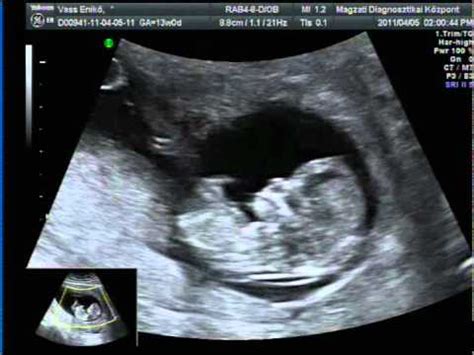

Ennek ellenére a várandós apáknak mindenképpen kialakulhat érzelmi kötődésük a terhességhez és a babához. Sok férfi számára kulcsfontosságú pillanat az első ultrahangkép megtekintése. Hirtelen valami valósággá válik: Egy apró emberke növekszik. Ekkor sok férfit különösen érdekelni kezdenek a mérhető részletek - például a baba mérete vagy súlya -. Az ilyen tények segítenek konkrétabbá tenni az elképzelhetetlent - és megnyithatják az utat a babával való érzelmi kapcsolat felé.

Bár a legtöbb vizsgálat a kismama testéről szól, a jelenléted az orvosi rendelőben üzenetértékű. A ultrahangos vizsgálatok során látott első képsorok a babáról nemcsak az anyának, hanem neked is segítenek a kötődés kialakulásában. Ott lenni, hallani a szívhangot és látni a mozgó apró végtagokat olyan közös élmény, amely mélyíti a szülővé válás érzését. Az orvosi konzultációk alkalmával te is kérdezhetsz. Gyakran előfordul, hogy a kismama az izgalomtól elfelejti feltenni a korábban kigondolt kérdéseit, ilyenkor jól jön, ha te észnél vagy. Készítsetek közösen egy listát a kérdésekről, és vezesd te a jegyzeteket az orvos tanácsairól. A szülésfelkészítő tanfolyamok látogatása szintén ajánlott a leendő apák számára. Ezek az alkalmak nemcsak a szülés folyamatáról adnak technikai tudást, hanem felkészítenek arra is, hogyan lehetsz hatékony segítő a vajúdás alatt. Megtanulhatod a légzéstechnikákat, a fájdalomcsillapító masszázsfogásokat és azt, hogyan képviseld a párod érdekeit a kórházi környezetben.